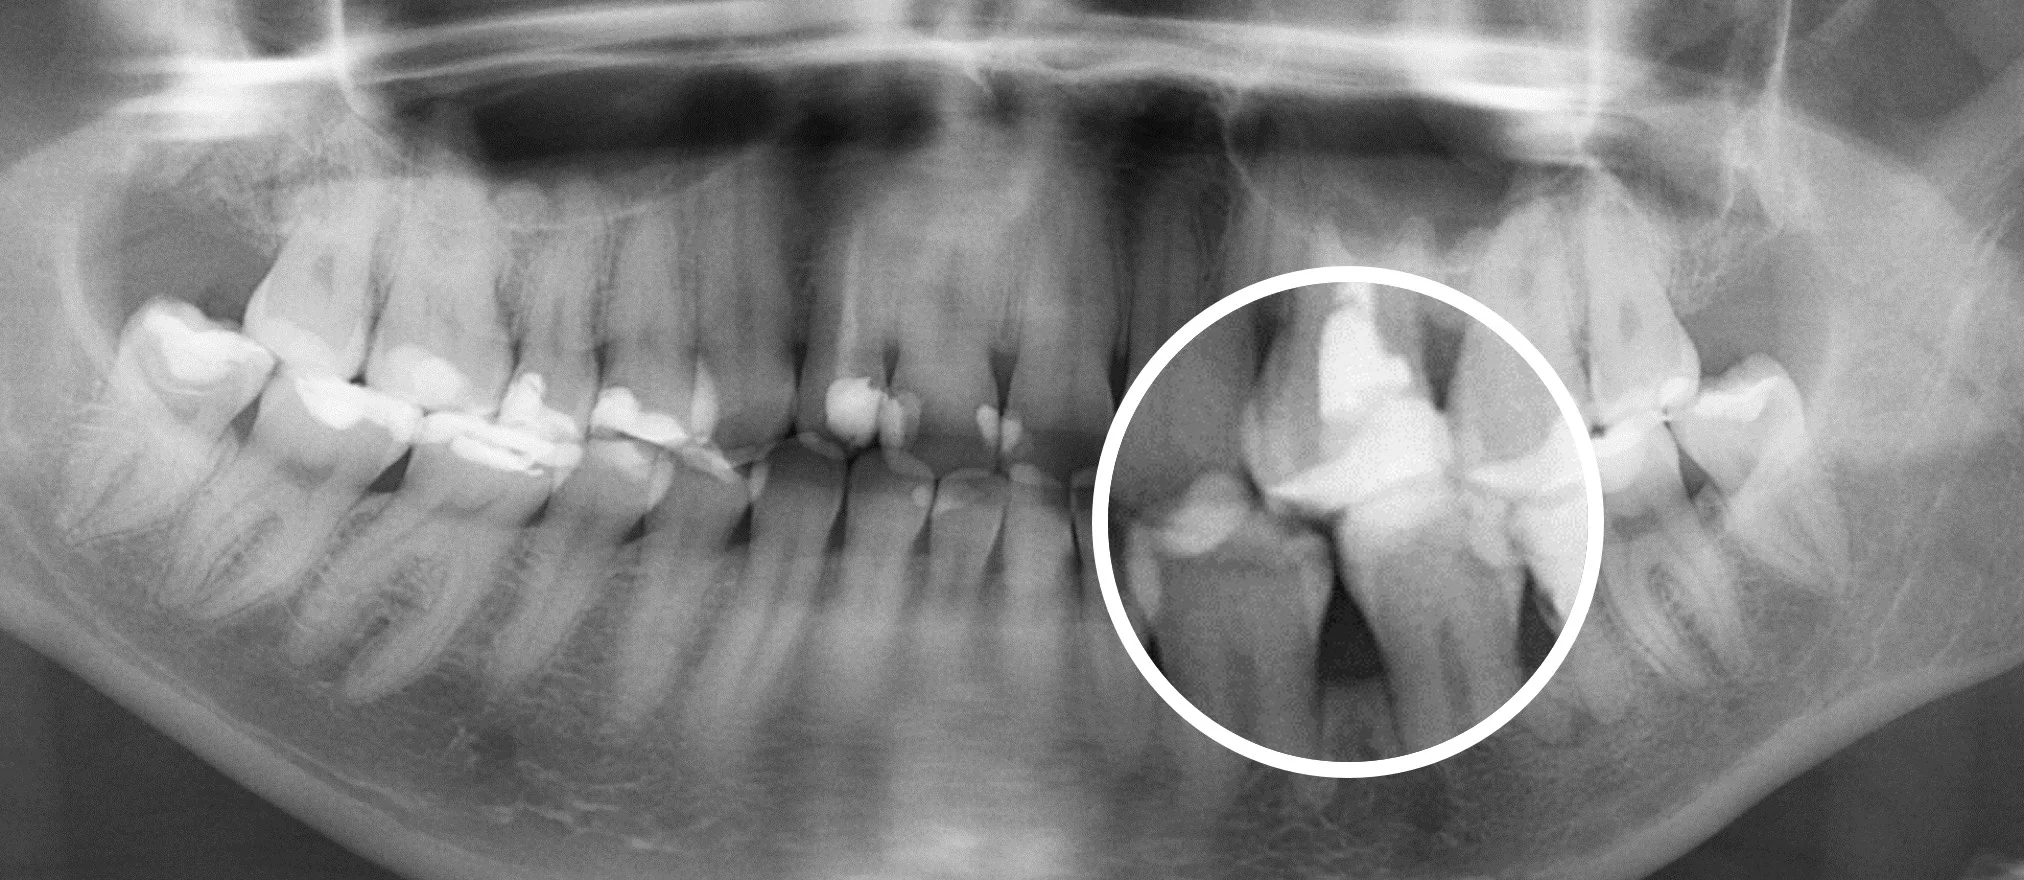

Стоматологическая нейросеть оценивает КТ и сверяет с информацией в своей обширной базе данных. Так она находит скрытые формы кариеса, периодонтиты и другие заболевания костной ткани, кисты, гранулемы и опухоли. Даже участки с минимальным подозрением отмечаются, чтобы ими занялся стоматолог.

- Загрузка результатов в ИИ. Отправляем ваши снимки в Diagnocat, который за 7 минут проверяет их по множеству параметров. В результате стоматолог получает визуализацию и презентацию всех обнаруженных проблем. Нейросеть подсвечивает, приближает и поясняет про состояние проблемных единиц.